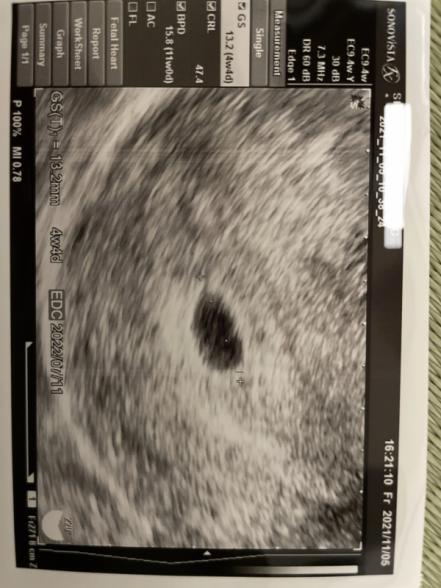

…が今日の検診で胎嚢13.5mmは確認出来たものの胎芽の確認は出来ませんでした。

また、エコー写真には4w4dと記載があります。